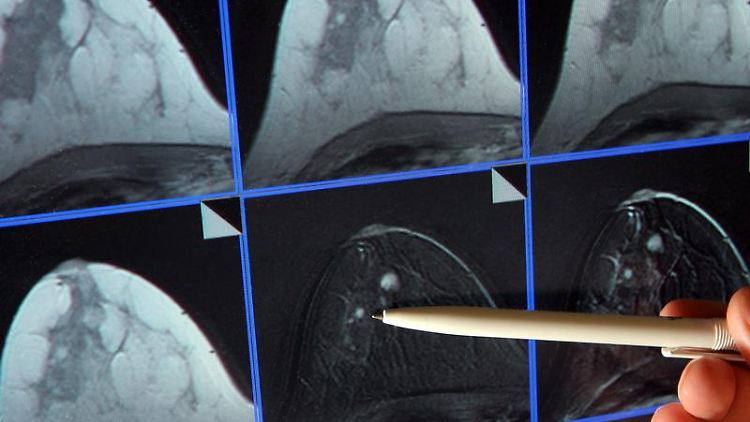

Jährlich erkranken mehr als 55.000 Frauen an Brustkrebs. Vielen von ihnen können kann mit einer entsprechenden Therapie geholfen werden. Doch die Nebenwirkungen sind oftmals gravierend. Mit einem neuen Verfahren, bei dem Tumoren während der Operation direkt bestrahlt werden, sollen Nebenwirkungen verringert und Therapiedauer gesenkt werden.

Eine kurzfristige Bestrahlung von Brustkrebs-Tumoren bereits während der Operation kann nach Expertenmeinung eine lange Strahlentherapie ablösen. Es handle sich um die sogenannte Intraoperative Radiotherapie (IORT). Bei der Methode erfasse ein Bestrahlungsgerät entsprechendes Gewebe direkt in der Operationshöhle, sagte Thomas Wiegel, Ärztlicher Direktor der Klinik für Strahlentherapie und Radioonkologie der Uniklinik, in Ulm.

Mit dieser Methode könne schon jetzt die Bestrahlung von Krebsgewebe nach der Operation durch die Haut um rund zwei Wochen verkürzt werden. Auch Hautveränderungen träten dann später auf. Der ärztliche Direktor Rolf Kreienberg, zugleich Präsident der Deutschen Gesellschaft für Gynäkologie und Geburtshilfe, verwies auf neue Forschungsergebnisse, nach denen bei der IORT-Therapie auch die Gefahr einer Wiedererkrankung sinken könne. Dennoch stehe weiter fest, dass der entscheidende Schlüssel zur Heilung des Brustkrebs die Früherkennung bleibe.